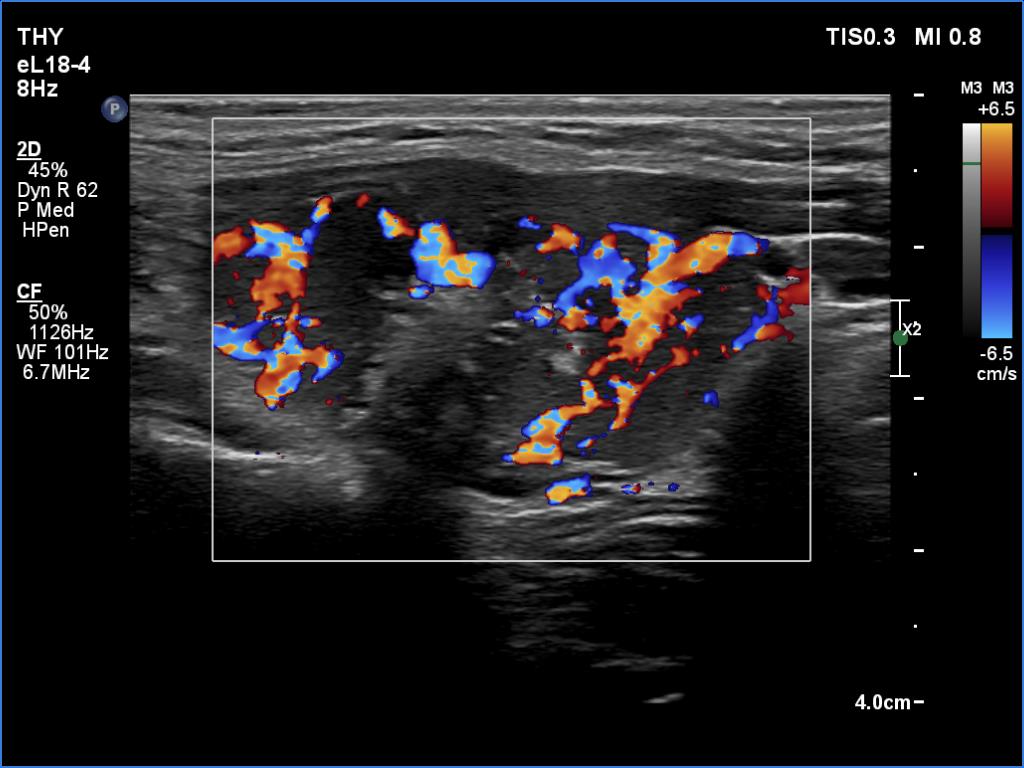

Ultrasonography. The thyroid was hypoechoic. The right lobe had a heterogeneous, dominantly minimally/moderately hypoechoic nodule in the ventrolateral part which had irregular borders and both perinodular and intranodular vascularity. There was another, hyperechoic star-like lesion in the central part of the right lobe. This lesion presented microcalcifications and was avascular. The left lobe was homogeneously hypoechoic.